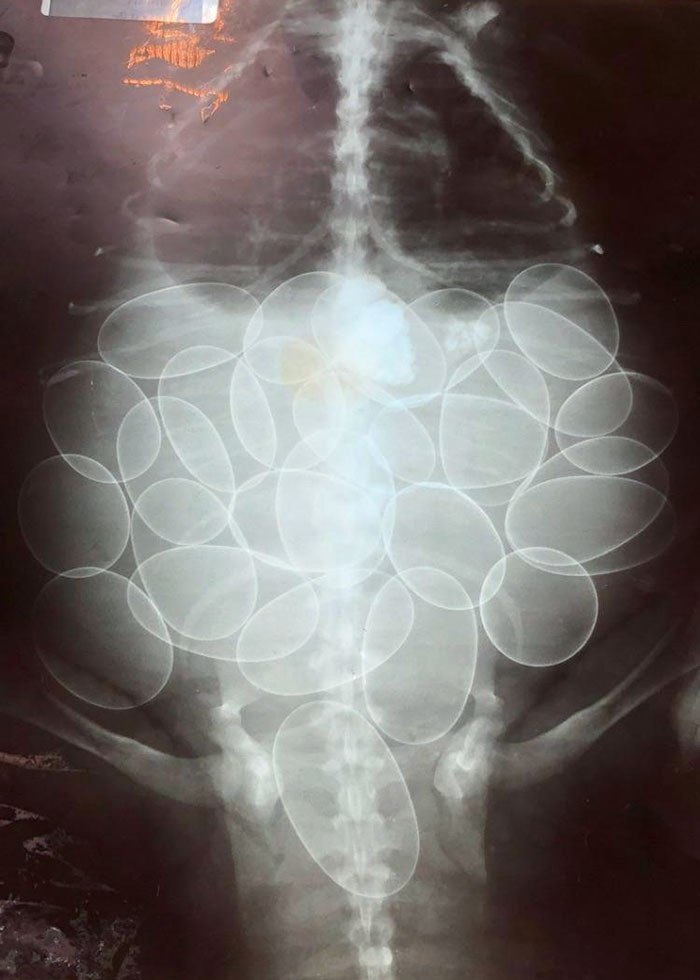

Gravid Ball Python X-Ray

My Snake Is Full Of Eggs